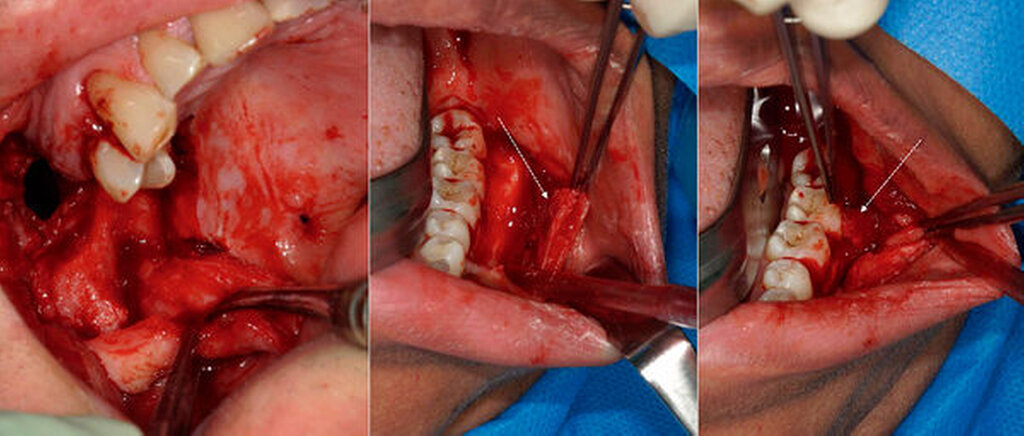

Nach marginaler Schnittführung von 34 bis 38 mit distaler Entlastung auf dem aufsteigenden Unterkieferast sowie subperiostaler Präparation (Abbildung 3a) konnte der Befund behutsam unter Schonung der Mukosa in toto ohne Sicherheitsabstand herausgelöst werden (Abbildungen 3b, 3c und 4). Ein zuführender Gefäßstiel wurde unterbunden und nach unauffälligem postoperativem Verlauf, insbesondere ohne Zeichen einer Nachblutung, konnte die Patientin noch am selben Tag in die Häuslichkeit entlassen werden. Histopathologisch zeigte sich ein weichgewebliches Exzidat mit Anteilen eines gutartigen vaskulären Tumors histologisch vereinbar mit einer fibroadipösen vaskulären Anomalie ohne Anhalt für Malignität.